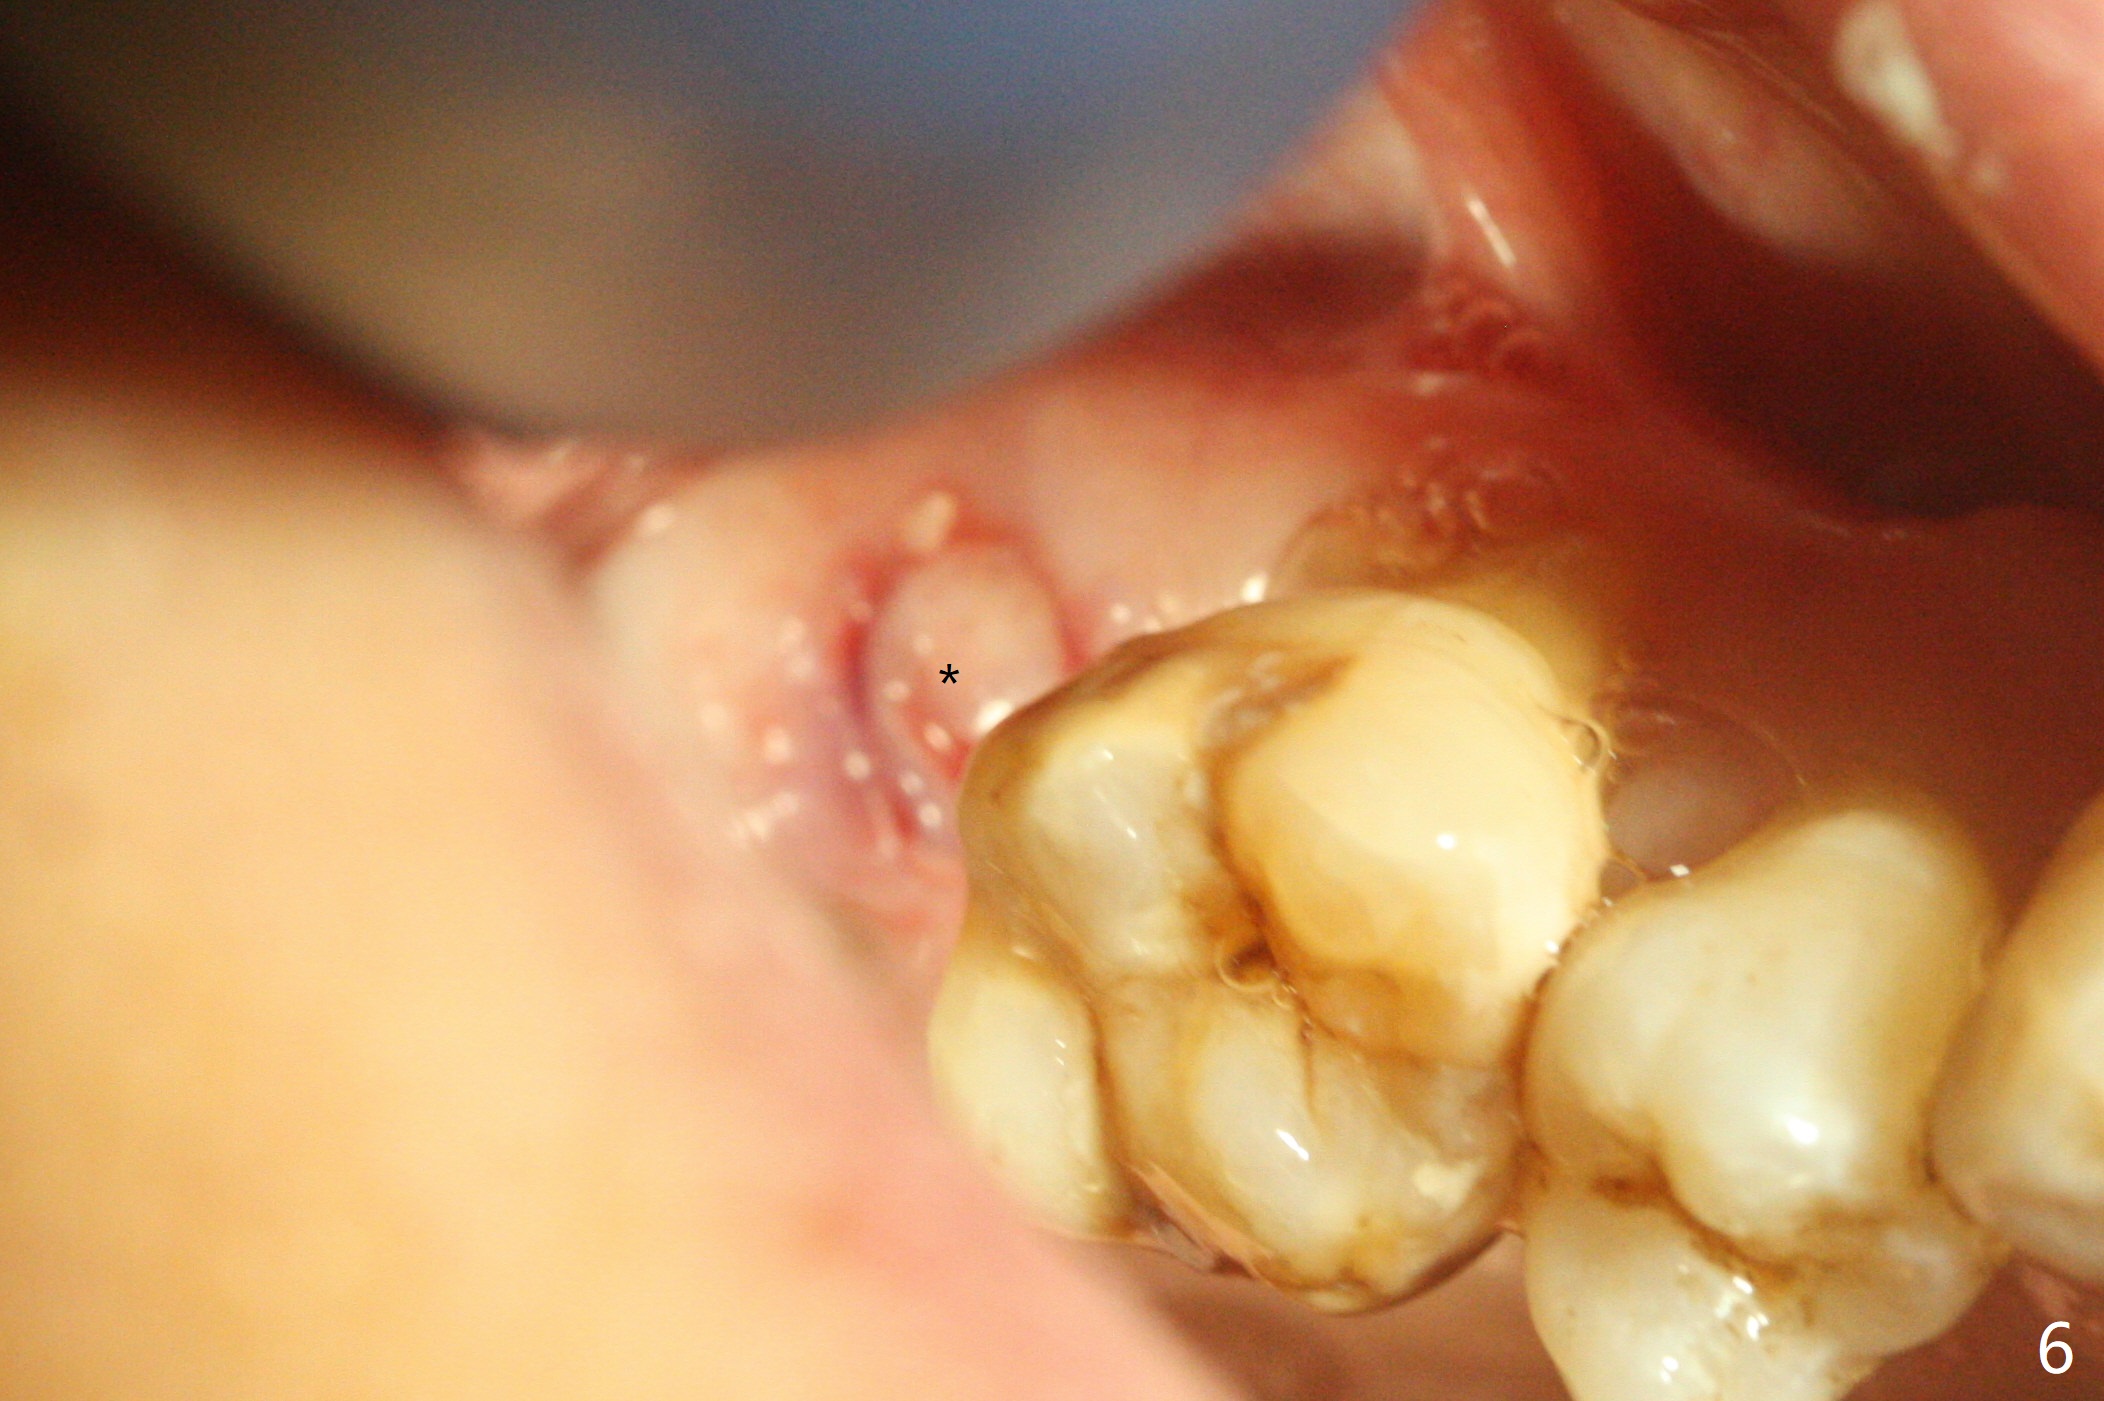

45岁女右上7严重骨质吸收,位点保存4-5个月,骨质高度增加,但是密度好像下降,准备上颌窦内提,同期种植,如果扭力太低,使用愈合帽,关闭伤口,最简易方法是利用环形刀保留牙龈。首先利用导板和导板环形刀(图一:好像绞肉机)在牙龈表面轻轻做一个标记(用手顺着金属圈按一下),然后取出导板,徒手使用锐利活检环形刀(图二),取出圆形牙龈,放入PRF上清液备用(图三)。接着放回导板完成提升(图四:*),不幸的是大一号正式植体无法取得稳定性,不得不取出,再大一号报废植体也无能取得固定,只好植骨(图五:*),放回保留的牙龈(图六:*),使用牙周胶水和树脂敷料固定。其实植骨前发现窦膜破裂,不过术后没有上颌窦并发症(术后服用激素)。术后7天树脂敷料稳定,局部卫生尚可(图七),准备术后一个月撤除敷料。